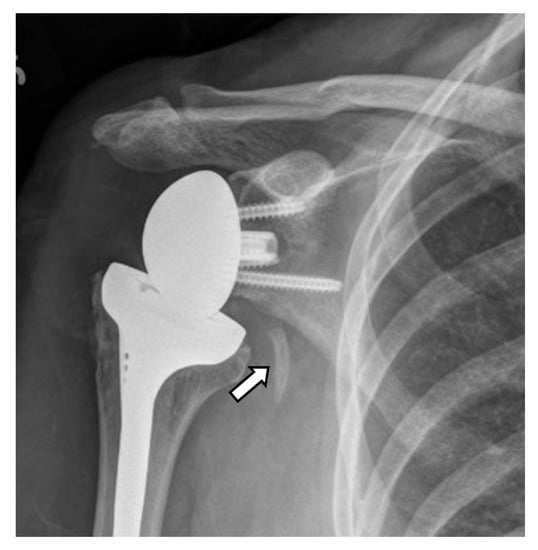

4.2.2. Stress Shielding and Fractures

4.2.3. Periprosthetic Joint Infection (PJI)